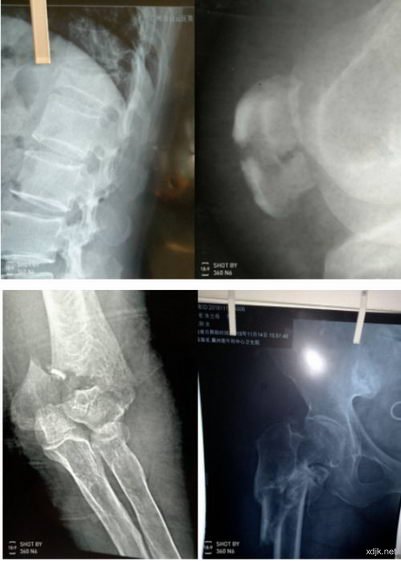

1、寇红魁,男,44岁,电话;180*****328,衡水市冀州区小寨乡寇杜村人,是一位货车司机,在一次装车过程中一捆钢材滚落,砸压全身,所幸钢材另一端落在马路牙,才捡回性命(患者自述)。钢材砸伤致18块骨骼不同程度的骨折,事故现场在天津静海,患者自述入院时血压为零,经医院抢救生命已无大碍,但是医生认为能够站起来的希望几乎为零。因患者家属入院期间询问我处,强烈建议其不要手术,半月后家属带患者来我处治疗。就诊日期为;2016年7月7日,经治疗五周便可以自由活动了,又治疗两周告愈。这一病例的特殊性是多处骨折,腰椎横突四块离位,用药后完全长好,离位的碎骨都已经自动复位,没有一处手术固定,完全靠药物的力量治愈,让一个不可能站起来的人站起来了,而且还未落任何后遗证,两个月后又回到工作岗位。患者家属由衷感谢,说;不但救了一个人,还挽救了一个家庭,因为此人为一家的主力。

3、徐瑞波,男,68岁,衡水冀州区门庄乡西徐家庄村人,电话;0318*****25,因车祸造成左腿胫骨两处,腓骨一处中段粉碎性骨折,三年来骨痂只有极少部分连接,多处求医问药无效。患者2015年1月14日来诊,望:病人的左小腿皮肤全部变为黑色;问:有无夜间疼痛,答有空心疼感不是太严重;从而得知其骨腔内瘀血斑已经形成,不久便会骨内坏死,面临的必是被截肢的厄运,医院也建议截肢。病人不忍心面对被截肢后的生活,所以苦求于我,我当时也没有完全把握能治好,所以商议试治四周,不见好转立即停药,商定后开始治疗,治疗三周皮肤开始退去黑色变为嫩色,有了好转迹象,治疗七周黑色的皮肤完全变得红润,除一小块约两公分之处没有变好,片子上显示是植假骨的位置,其余完全长好,骨痂也都长好了,这也是我的医疗奇迹,把将要截肢的病人真的治好了。这也是我内心最为喜悦的一例。